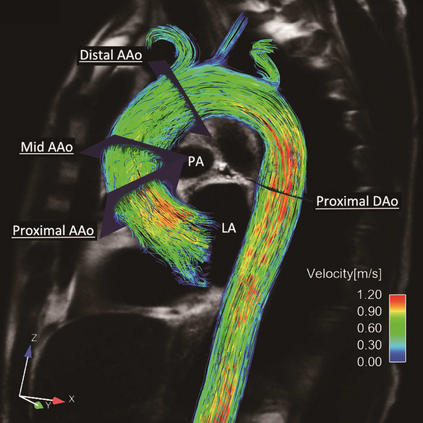

The choice of appropriate boundary conditions is a fundamental step in computational fluid dynamics (CFD) simulations of the cardiovascular system. Boundary conditions, in fact, highly affect the computed pressure and flow rates, and consequently haemodynamic indicators such as wall shear stress, which are of clinical interest. Devising automated procedures for the selection of boundary conditions is vital to achieve repeatable simulations. However, the most common techniques do not automatically assimilate patient-specific data, relying instead on expensive and time-consuming manual tuning procedures. In this work, we propose a technique for the automated estimation of outlet boundary conditions based on optimal control. The values of resistive boundary conditions are set as control variables and optimized to match available patient-specific data. Experimental results on four aortic arches demonstrate that the proposed framework can assimilate 4D-Flow MRI data more accurately than two other common techniques based on Murray's law and Ohm's law.

翻译:选择适当的边界条件是心血管系统计算流体动态(CFD)模拟的基本步骤。事实上,边界条件对计算的压力和流动率产生很大影响,从而对临床感兴趣的壁剪裁压力等血液动力指标产生很大影响。设计选择边界条件的自动化程序对于实现可重复的模拟至关重要。然而,最常见的技术并不自动吸收特定病人的数据,而是依靠昂贵和耗时的人工调控程序。在这项工作中,我们提出一种技术,用于在最佳控制的基础上自动估计外部边界条件。抵抗边界条件的价值被设定为控制变量,并优化以与现有特定病人的数据相匹配。四条方形拱门的实验结果表明,拟议的框架可以比根据默里法律和奥姆法律的其他两种常见技术更准确地吸收4D-Flow MRI数据。